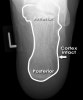

X-ray : Normal calcaneus(Axial view)

X-ray : 종골 골절(Calcaneal fracture)****- Axial view

On the axial view look for fracture lines and breaks in the cortex

Loss of smooth cortical edge (yellow line)